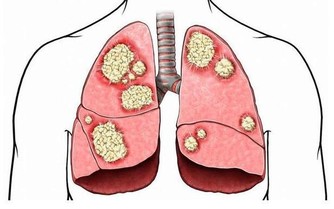

1、呼吸系統

呼吸系統腫瘤主要是指肺癌。經過手術切除或放化療之後,病人大多有不同程度肺功能的障礙,鍛煉項目的選擇應以恢復或增強肺功能為目的,鍛煉方式主要有吹氣球和腹式呼吸。吹氣球用普通氣球即可,要求連續吹,盡量一次吹鼓。腹式呼吸可將手放在腹部,要求吸氣時腹部鼓起,呼氣時腹部落下,在整個呼吸過程中胸廓變化不大。

2、在運動過程中,要特別注意到對於患有不同腫瘤的病人,應充分考慮到疾病與治療所造成的後果,而區別對待。例如:肺癌患者肺葉切除術後要加強胸部的運動鍛煉來改善呼吸功能,乳腺癌根治術後要加強上肢的活動等。